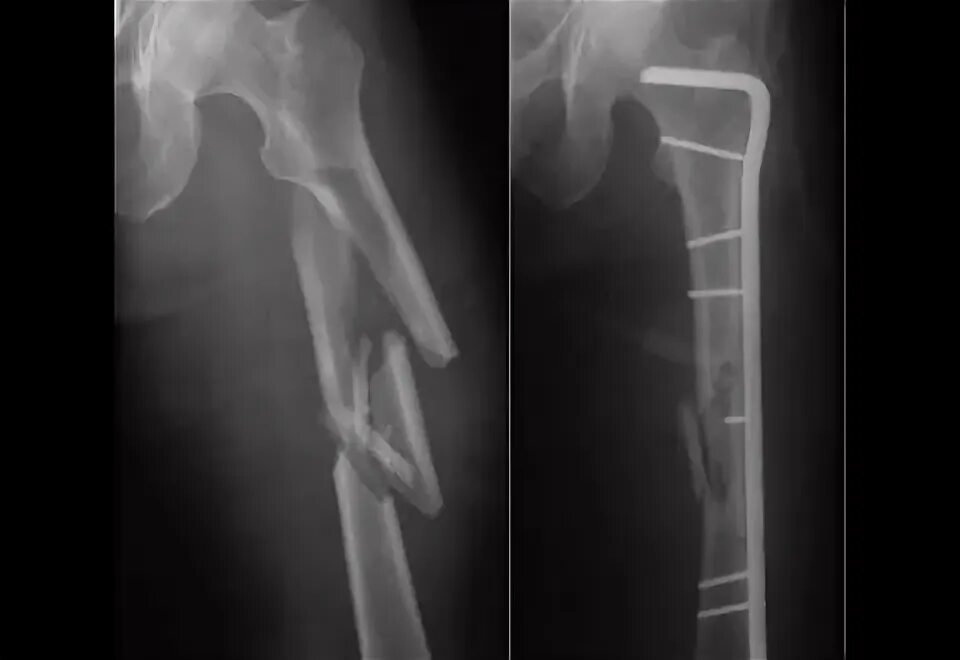

Патологический перелом бедра